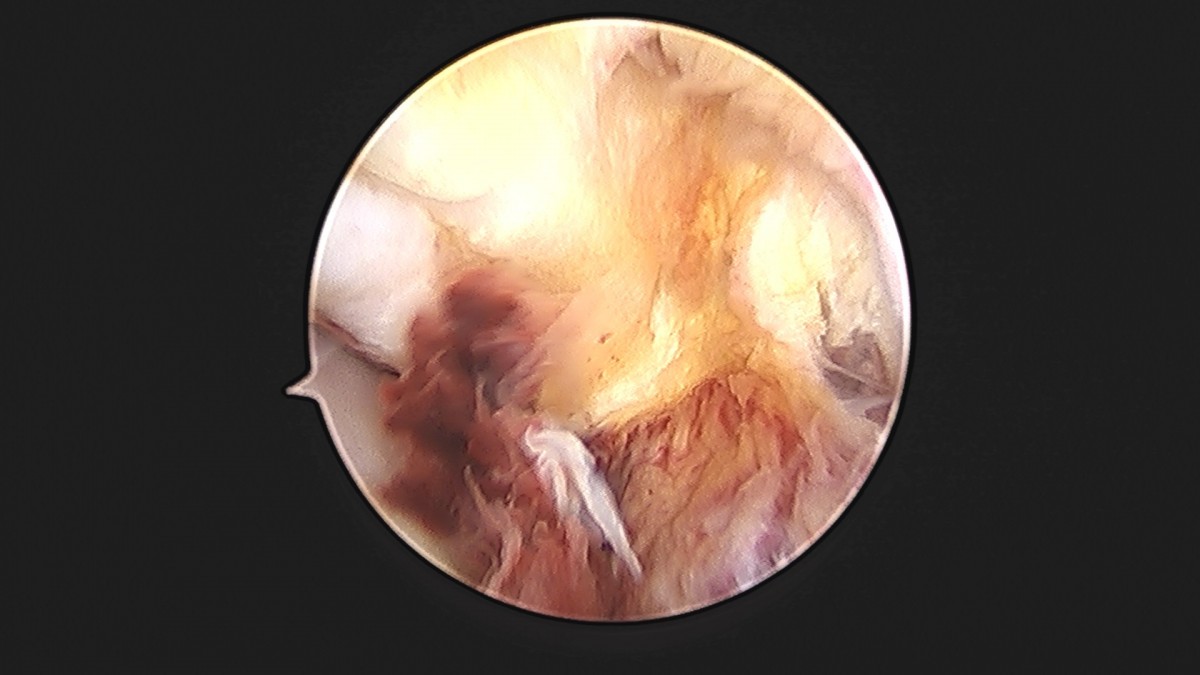

이재상원장님 발목 인대 봉합술 박찬O 환자

dae765e4d9ac96aee867c9d6292d8784_1758007285_6203.jpg